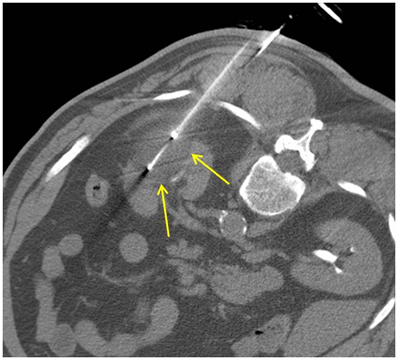

在電腦斷層導引下,將冷凍探針經過皮膚插到腫瘤組織中。冷凍探針在針尖可形成一圓型的超低溫範圍,當溫度低於-20℃即可造成細胞壞死,達到治療目的。因冰塊在電腦斷層下清晰可見,因此可確認治療範圍完全涵蓋腫瘤,且未傷害正常組織。冷凍治療具有包括侵入性極小,無痛,可保留腎功能等好處,於2006年通過衛生署認證,已證實為一安全有效的腎臟腫瘤治療方法。

4.在電腦斷層的導引下將冷凍探針插進腫瘤。

5.開始冷凍治療,共約30分鐘。